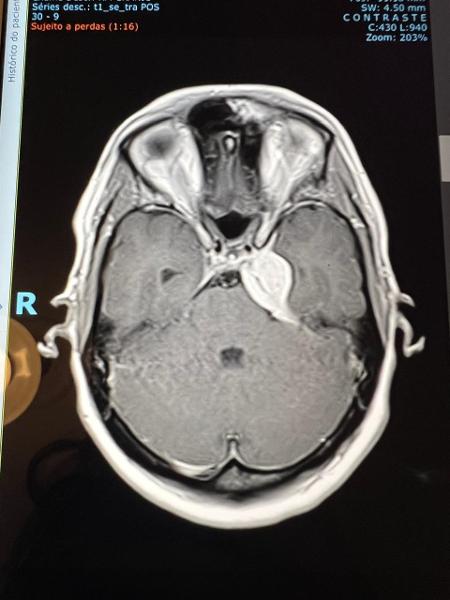

O neurologista me explicou que o tumor estava em uma área muito ruim, atrás do olho esquerdo, na base do crânio. Estava comprimindo a carótida e o nervo responsável pela pupila e pelos movimentos do rosto. Por isso minha visão estava embaçada.

Niemeyer explicou que esse tipo de tumor é mais comum em mulheres e que só faria cirurgia se houvesse risco para o nervo óptico. Ainda bem, não havia. Minha indicação foi fazer radioterapia.

Comecei a radioterapia no dia de São Francisco de Assis —o protetor dos animais—, uma ironia do destino. Após sete sessões, minha pupila voltou a reagir e recuperei a visão. Fiz 27 sessões ao todo e, três meses depois, um novo exame mostrou regressão do tumor: de um limão para o tamanho de uma azeitona, uma redução de 64%.

O tumor de Luiza, um meningioma, é comum em adultos jovens e mais frequente em mulheres, atingindo a meninge, camada protetora do cérebro. "Esses tumores benignos são, muitas vezes, descobertos por acaso. Dependendo do tamanho, idade, localização e sintomas, definimos o tipo de tratamento", diz Maldaun.

Em alguns casos, é possível realizar cirurgia; em outros, o tratamento é feito com radioterapia, como no caso de Luiza. O acompanhamento deve ser feito para o resto da vida.